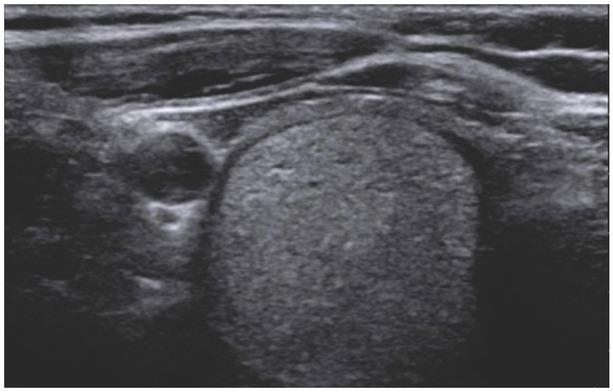

Fig. 1